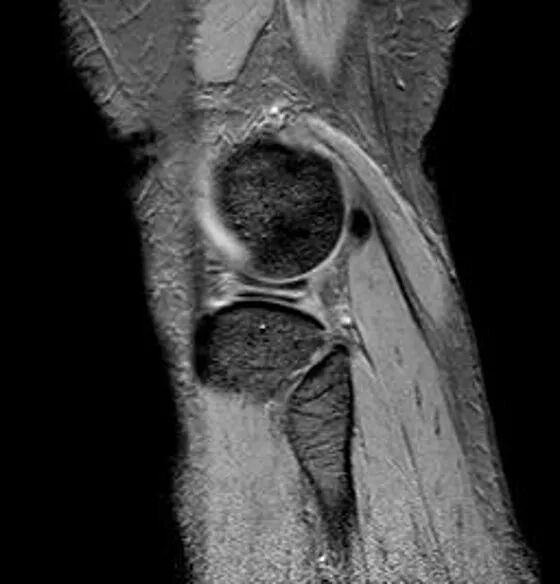

桶柄状撕裂MRI表现

1、宽度减小,在通过半月板体部的冠状面上蝶形消失,同时可见内移的半月板位于髁间窝、交叉韧带旁2、矢状面示残余的前角或后角变小或截断3、半月板前(后)角增宽或双半月板前(后)角征4、双前交叉韧带或双后交叉韧带征

半月板撕裂:桶柄状撕裂(双前角征)

桶柄状撕裂(双后交叉韧带征)

桶柄状撕裂:双前交叉韧带征